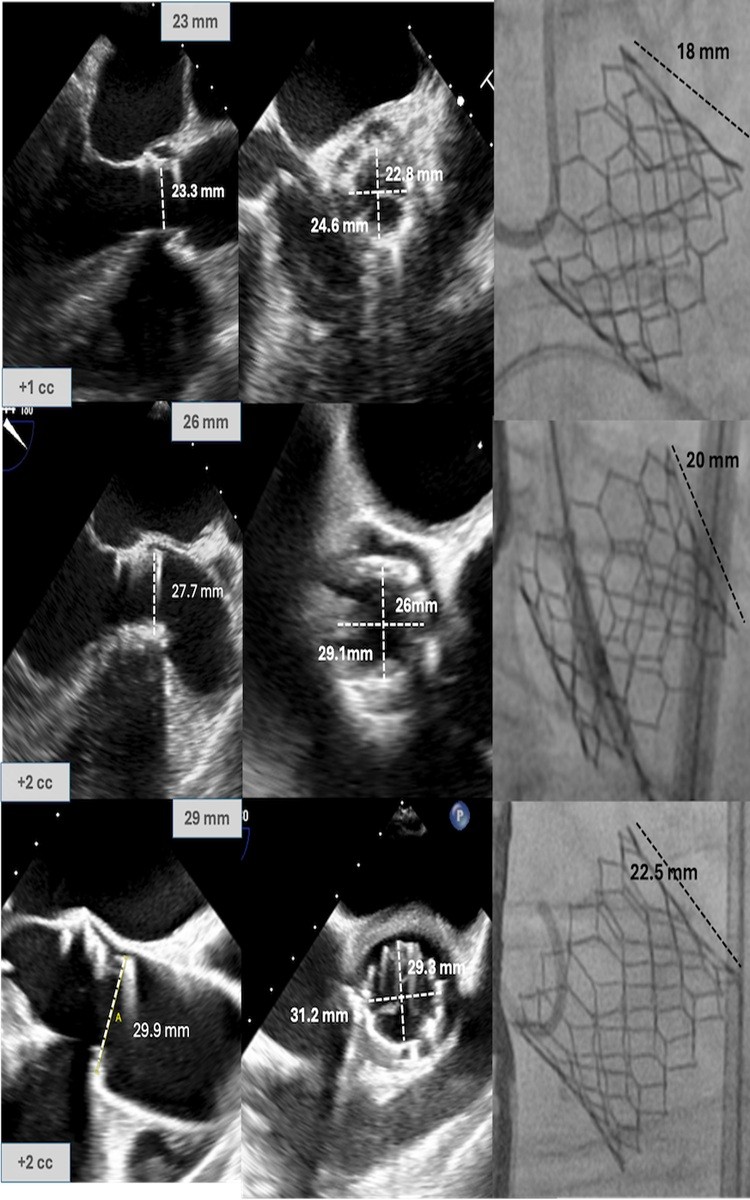

Resultados: Se incluyeron 118 pacientes en el estudio. 56 en los que la prótesis se implantó a volumen nominal y 62 en los que el implante se realizó con volumen adicional (39 con 1 cc extra, 19 con 2 cc extra y 4 con 3 cc adicionales). No existieron diferencias demográficas entre los grupos. Los pacientes en los que se realizó sobreexpansión de la prótesis presentaban un diámetro del anillo aórtico mayor respecto al grupo nominal (para cada tamaño protésico). La prótesis presentó también un diámetro significativamente mayor tras el implante. La sobreexpansión no se asoció a un mayor grado de insuficiencia aórtica (ni intra ni periprotésica) ni existieron diferencias en el gradiente transvalvular medio posimplante. Las complicaciones fueron similares entre ambos grupos.

Medidas del diámetro de la prótesis en pacientes con sobreexpansión durante el implante (prótesis de 23/26 y 29 mm respectivamente).

Conclusiones: El TAVI con prótesis de Edwards con un volumen de inflado superior al nominal parece seguro, y podría ser adecuado en pacientes con medida del anillo correspondiente a dos tamaños protésicos.